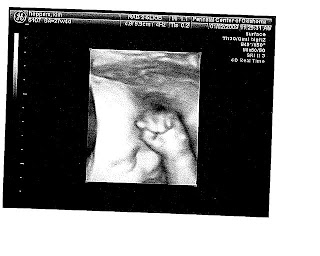

The best news is that we got to see our precious baby last week during an ultrasound and everything checked out perfect--we have a healthy little one cooking in there! The doctor let us watch "real time" in 4D and it was truly amazing to watch as the baby moved its mouth, arms, hands, etc. We are still on "Team Green" and didn't find out the gender (as hard as it was for me to not peek!). In only 12 more weeks, we will get to meet this little surprise miracle and Trevor will get to make his "It's A ......" announcement.

Here are a few pictures from the ultrasound (please excuse the scanning job). There are a couple that look just like Addie when she was born. :)